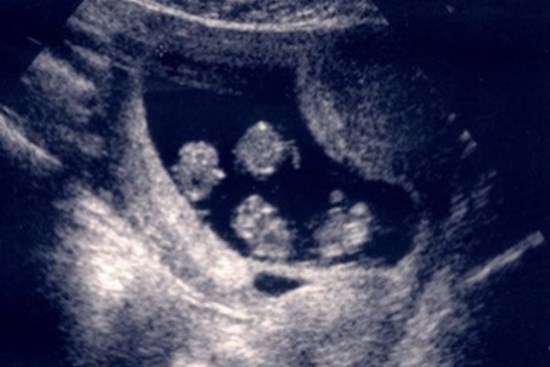

Siêu âm ở tuần thứ 6, bác sĩ thông báo một tin khiến bà mẹ run lẩy bẩy, sau đó ngồi khóc suốt 1 giờ đồng hồ

Cặp vợ chồng hào hứng đi siêu âm rồi bất ngờ ngã ngửa khi nghe bác sĩ thông báo một tin "động trời".